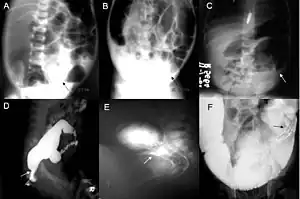

Barium enema in neonate with Hirschsprung disease

A: Plain abdominal radiograph showing a PARTZ at rectosigmoid, arrow. B: Plain abdominal radiograph showing a PARTZ at midsigmoid, arrow. C: Plain abdominal radiograph showing a PARTZ at descending colon, arrow. D: Contrast enema showing a CETZ at rectosigmoid, arrow. E: Contrast enema showing a CETZ at midsigmoid, arrow. F: Contrast enema showing a CETZ at descending colon, arrow.